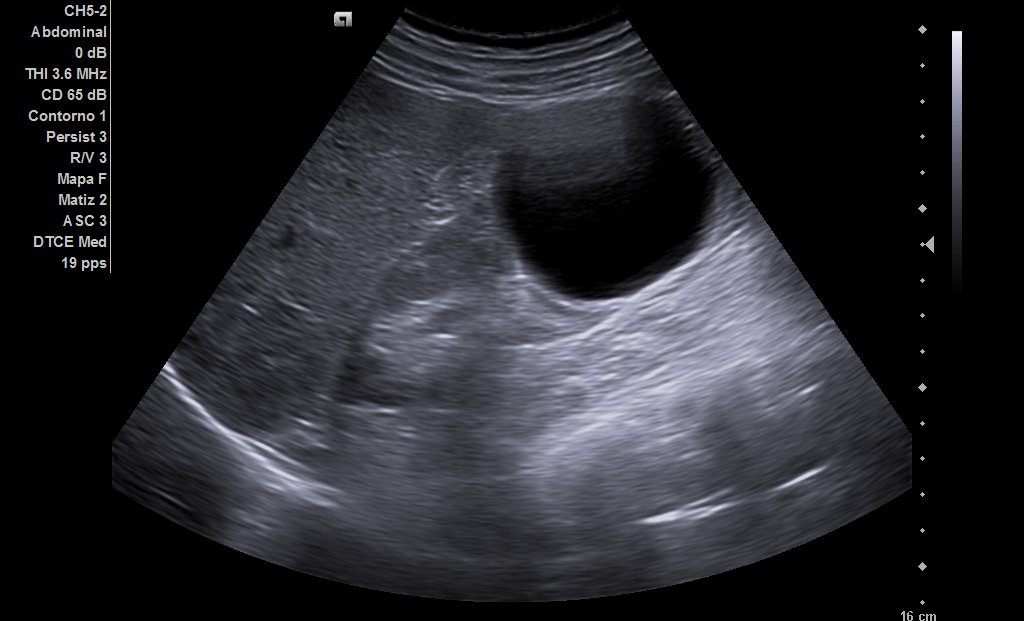

Riñones de tamaño y ecoestructura normales, con buena diferenciación parénquima-seno en polo inferior de riñón derecho, quiste simple de aproximadamente 6 centímetros de eje mayor (ya conocido) y en riñón izquierdo, quiste cortico-sinusal de menos de 2 cm (también conocido). Próstata de 44 gramos. En hipocondrio izquierdo observamos imagen redondeada con contenido ecogénico, con tractos hiperecogénicos en su interior que podría corresponderse a dilatación ángulo esplénico de colon.